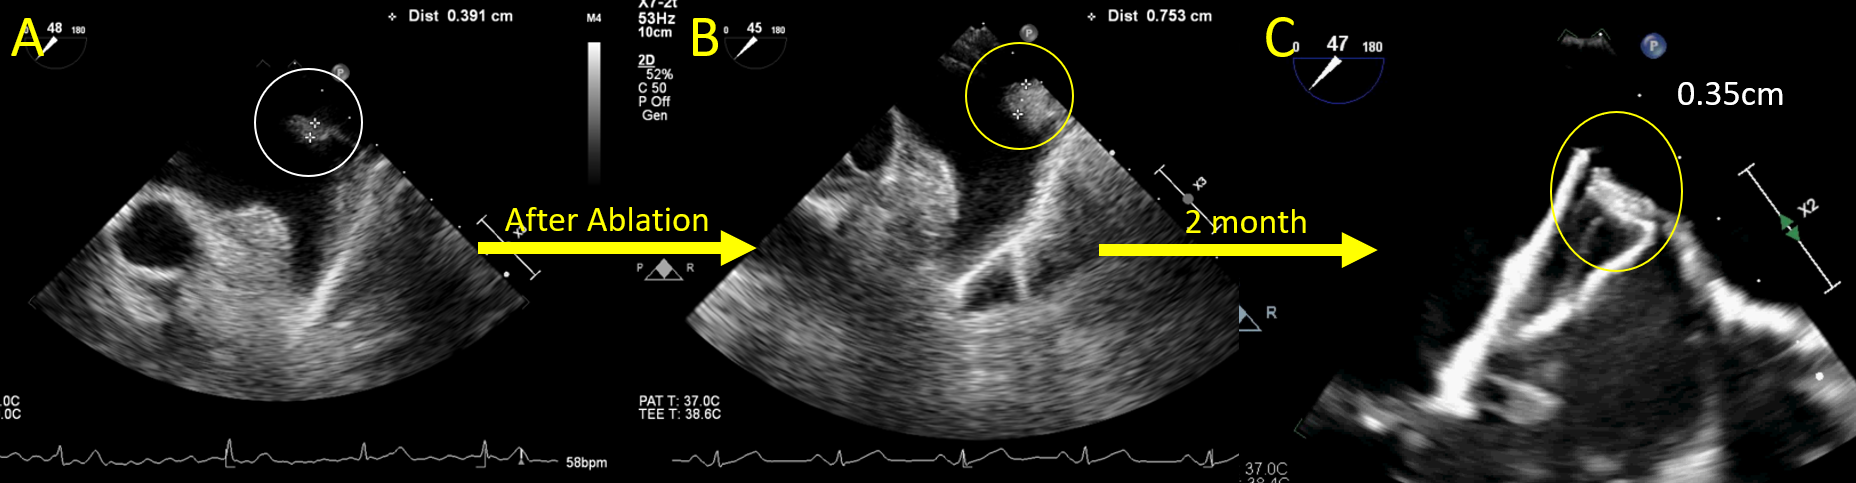

The patient presented is a 73-year-old woman with a 6-month history of persistent AF and a CHA2DS2-VASc score of 4. Pulmonary vein antral isolation (PVAI) was first achieved using the 31-mm FARAPULSE PFA catheter (Boston Scientific). Significant pulmonary ridge edema was observed immediately after ablation (Figure 1A and B). The diameter of the LAA landing zone was 24 x 21 mm on the 3-dimensional trans-esophageal echocardiography (TEE), measured at a mean left atrial pressure of 14 mm Hg. A 28-mm Amplatzer Amulet device (Abbott) was deployed at an optimal position in the LAA under TEE and fluoroscopy guidance (Video 1). The device was stable on a tug test with satisfactory compression and no residual flow (Figure 2A, B, and E; Video 2). However, follow-up TEE performed 2 months after the procedure showed proximal migration of the LAAO device (Figure 2C and D, Video 3) with resolution of pulmonary ridge edema (Figure 1C). Another TEE repeated 1 month later showed a stable device position. In view of the device migration with a potential sealing issue and uncertain device endothelialization, the patient was advised to continue oral anticoagulant therapy for stroke prophylaxis.

Our case showed that PVAI with PFA resulted in significant pulmonary ridge edema. We speculate that the proximal migration of the device was attributed to the resolution of significant ridge edema after PFA. Pulmonary ridge edema has been postulated to be associated with the LAAO device shouldering with PDL following the combined procedure of cryoballoon ablation and LAAO using a Watchman device (Boston Scientific).2 While upsizing the LAAO device may help compensate for the edematous changes, serious complications such as device dislodgement, pressure necrosis, and perforation should be considered. Deep device implant has been suggested in the hope of avoiding the edematous ridge, but it has recently been shown to be associated with a higher risk of device-related thrombus due to larger uncovered LAA areas.3 Both lobe-disc and plug devices have been used in combined procedures. Lobe-disc devices may be more likely to impact nearby structures including the ridge when compared to plug devices, but data comparing the procedural success and clinical outcomes of 2 types of devices in combined procedures remains limited.